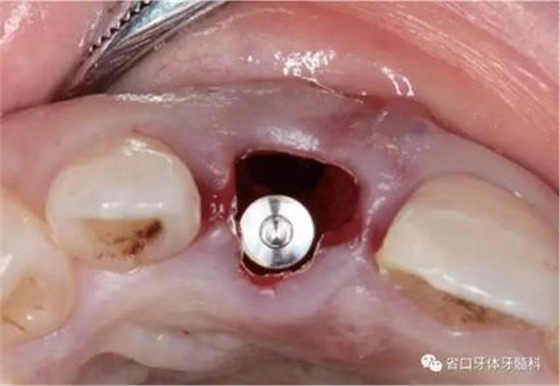

(1)微創(chuàng)拔牙及即刻種植:術(shù)前拍攝口內(nèi)照及實(shí)施牙周基礎(chǔ)治療。常 規(guī)消毒鋪巾阿替卡因局麻下微創(chuàng)拔除上頜右側(cè)中切牙,搔刮拔牙窩及根尖肉 芽組織。探測牙槽骨唇側(cè)骨壁及鄰面牙槽嵴完整,牙齦無撕裂。不翻瓣下于上頜右側(cè)中切牙缺隙近遠(yuǎn)中中點(diǎn)的腭側(cè)牙槽骨及根方定位,按照逐級預(yù)備的原則,緊貼牙槽窩腭側(cè)骨壁制備種植窩洞,植入Zimer®3.7mm×13mm TSV種植體1顆,植入扭矩>35N·cm,以O(shè)sstell測量種植體的ISQ值為68。 種植體平臺位于唇側(cè)齦緣中點(diǎn)下3mm,與唇側(cè)骨壁內(nèi)側(cè)面形成的跳躍間 隙約2mm,置入Bio-Oss®細(xì)顆粒骨粉0.25g,上愈合基臺關(guān)閉創(chuàng)口。術(shù)后 CBCT檢查顯示:種植體利用牙槽窩根方骨質(zhì)固位,緊貼牙槽窩腭側(cè)骨壁, 其唇側(cè)面與牙槽窩唇側(cè)骨壁的內(nèi)側(cè)面所形成的跳躍間隙(約2mm)可見顆 粒狀顯影物充填。牙槽窩的唇側(cè)骨壁及唇側(cè)倒凹無缺損穿孔。

圖16 跳躍間隙植骨

圖17 跳躍間隙植骨

圖18 測量ISQ值

圖19 術(shù)后MCT

圖20 術(shù)后開窗式取模轉(zhuǎn)移